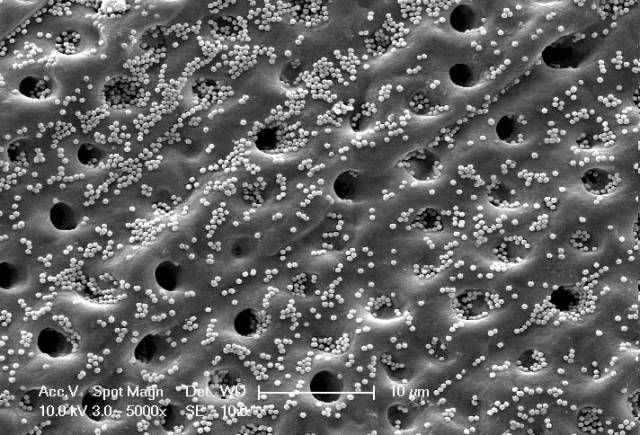

Interdisciplinary research between Dentistry and Chemistry has shown how the development of coated silica nanoparticles could be used in restorative treatment of sensitive teeth and preventing the onset of tooth decay. The work was undertaken […]